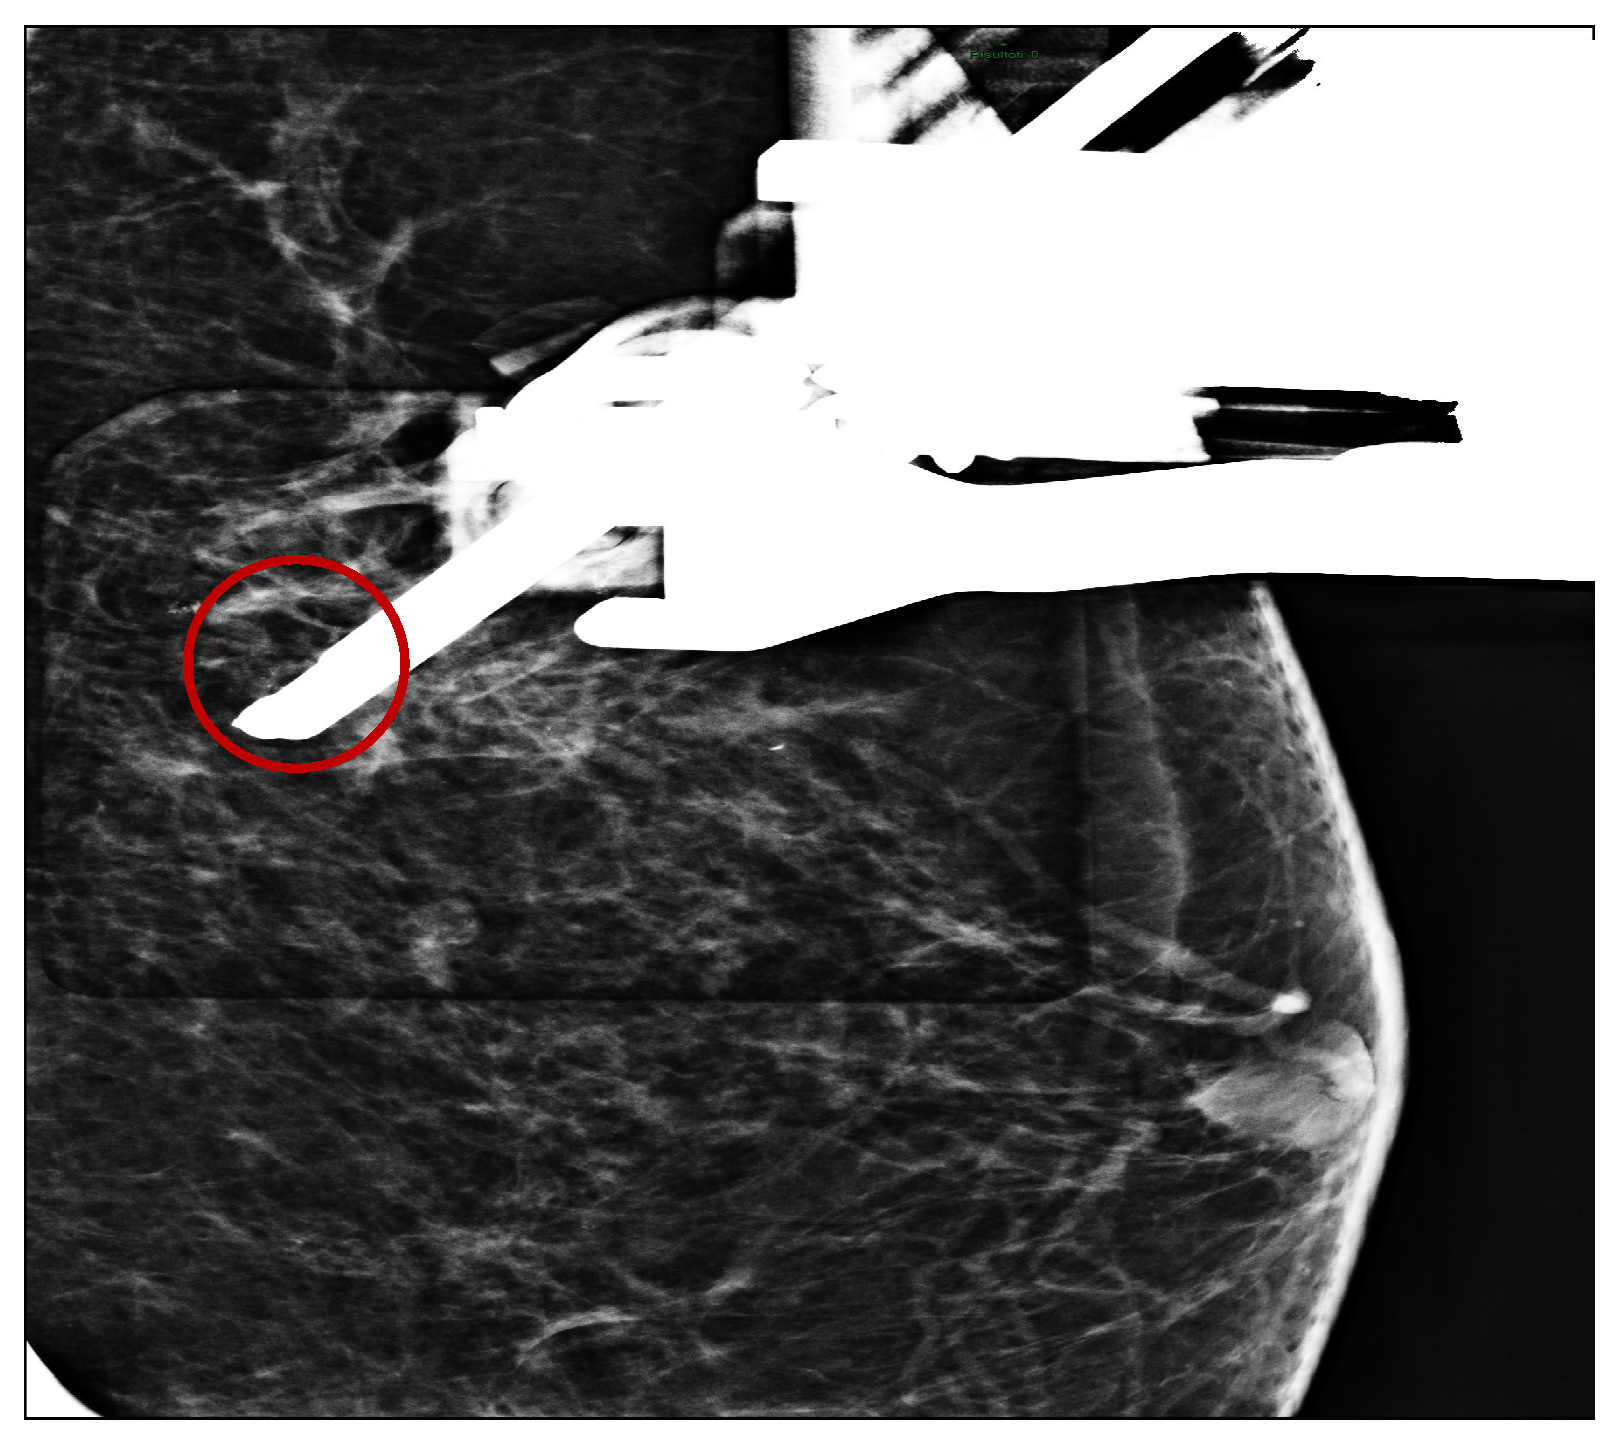

After the administration of a local anesthetic (5 cc of lidocaine + adrenaline 20 mg/mL + 5 mcg; adrenaline induces local vasoconstriction by decreasing bleeding), four tissue samples were taken under mammography guidance VABB with an 11 gauge needle in the microcalcification’s area located in the upper-outer quadrant (Figure 1 and Figure 2).

Figure 1.

Cluster of microcalcifications detected. (Red circle).

Figure 2.

VABB positioned in the microcalcifications spot. (Red circle).